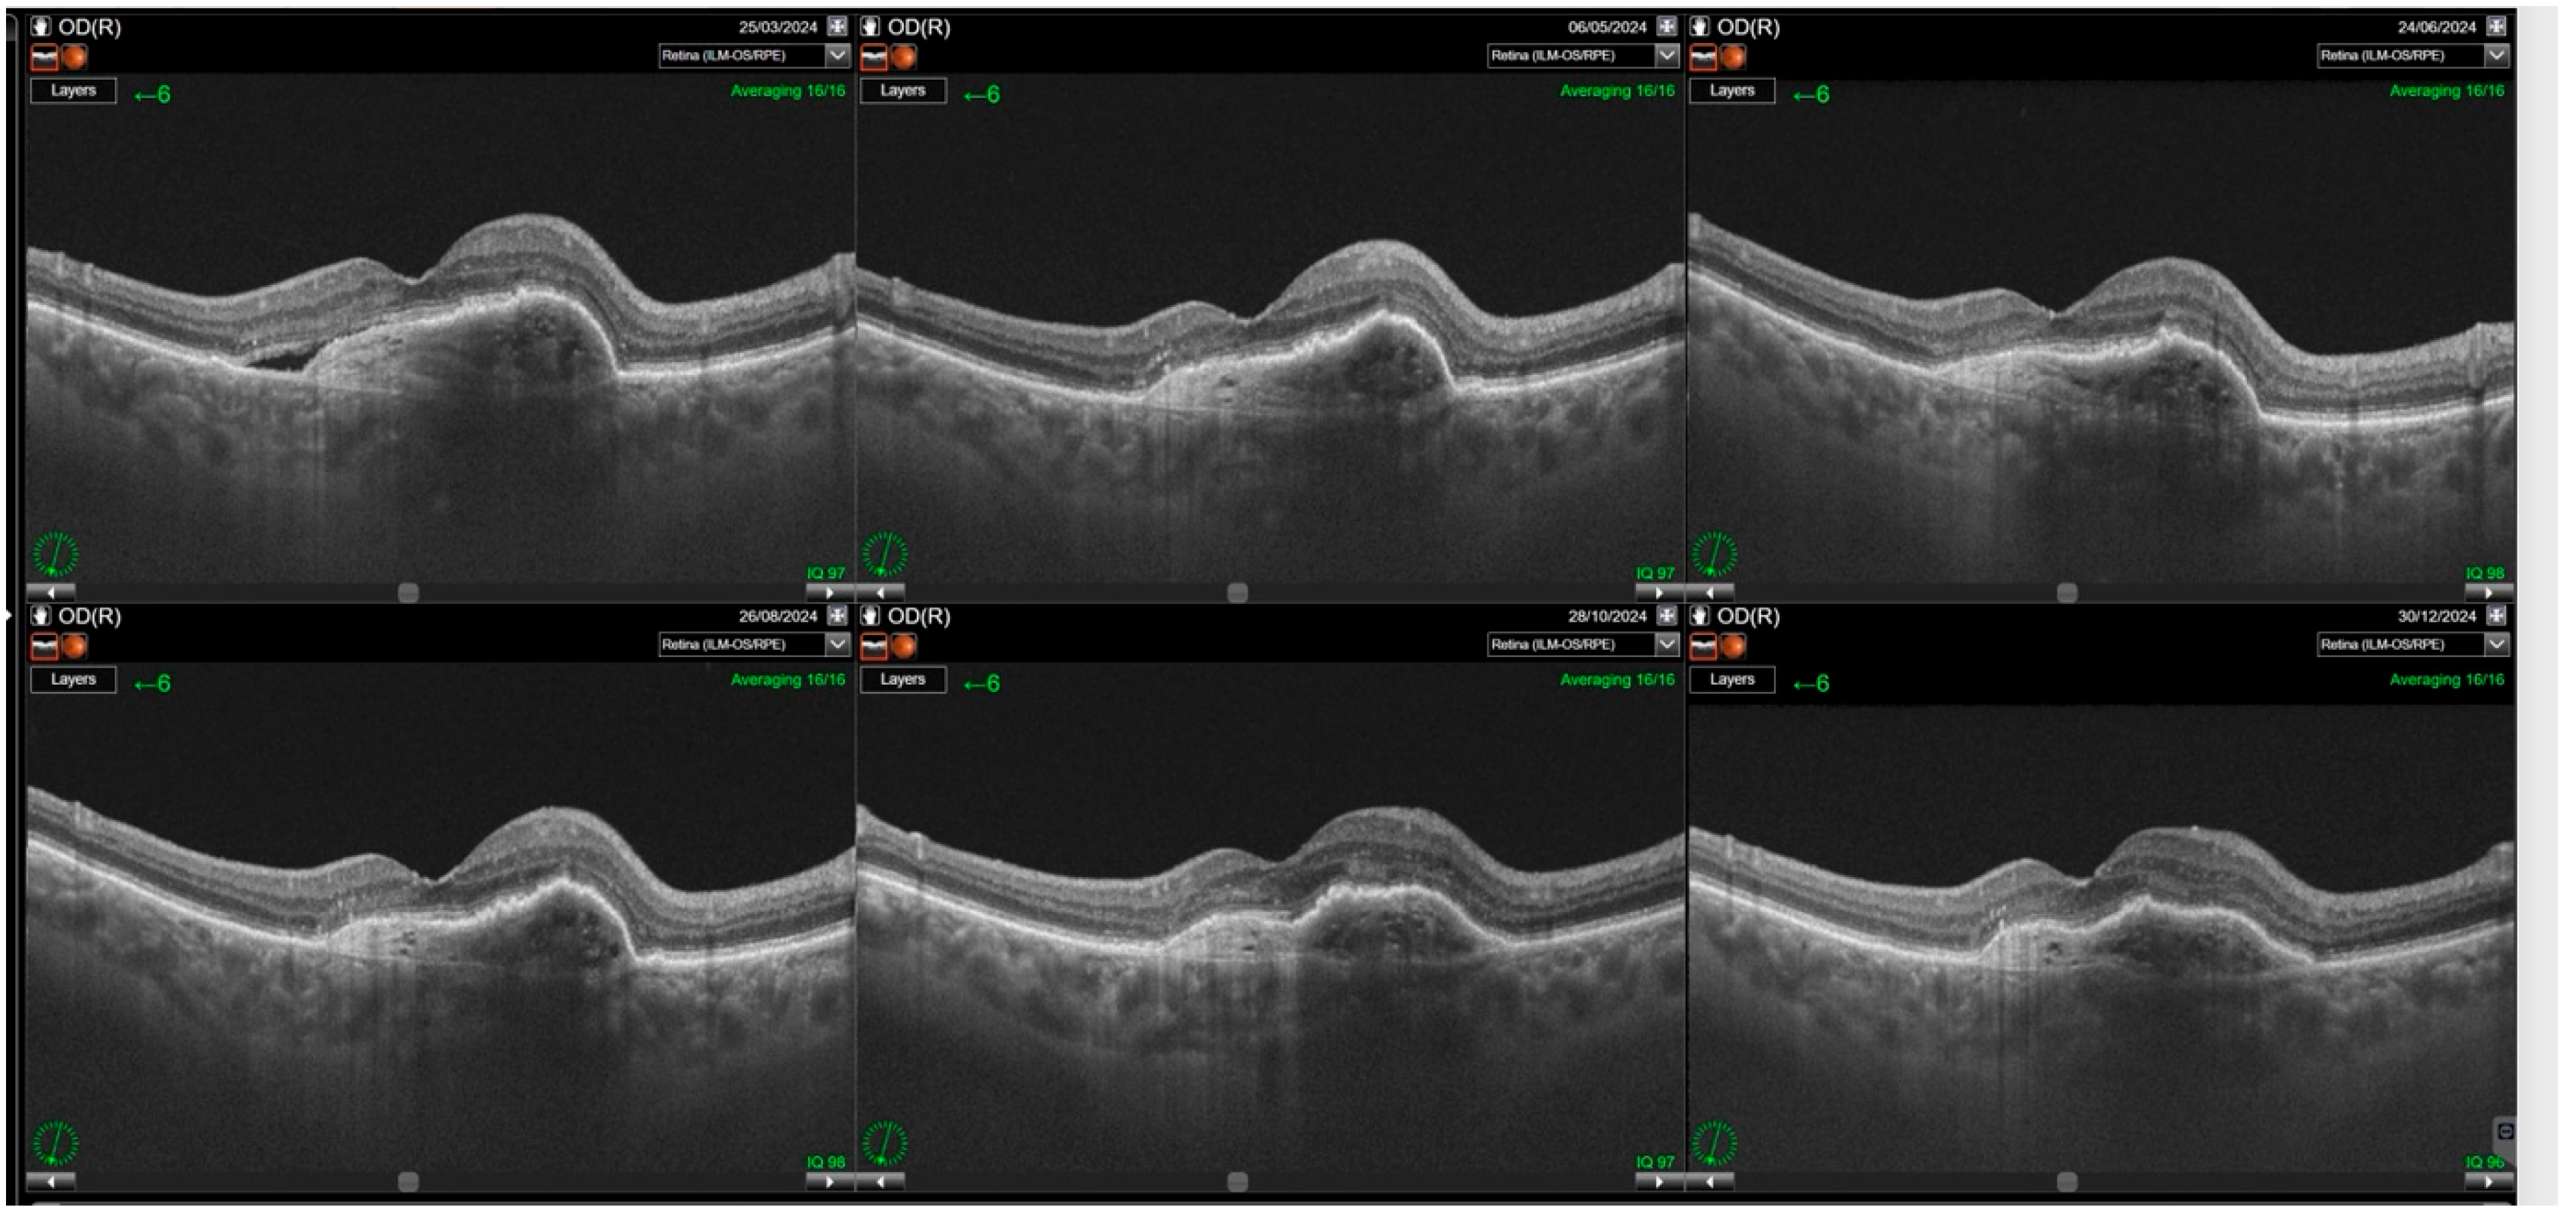

Switching to faricimab in the treatment of nAMD produced anatomical improvements that followed a distinct temporal pattern during post-switch follow-up. By the end of the observation period, retinal morphology demonstrated clear improvement, driven primarily by a reduction in SRF. In contrast, changes in IRF were not statistically significant, while reductions in PED reached borderline statistical significance at the final visit (p = 0.0455). The greatest morphological benefit was observed at visits 2 and 3, corresponding to the second phase of the loading regimen, during which the reduction in residual IRF was also statistically meaningful. However, as treatment intervals were subsequently extended, the magnitude of these anatomical gains gradually declined (Table 2). Loss of early improvement after the loading phase was also evident in SS-OCT parameters, specifically CST (Table 3; Figure 1). Retinal thickness showed a significant reduction compared with baseline during the loading phase, but this benefit gradually waned and was no longer present at the end of follow-up. Examples of SS-OCT scans at baseline and through the follow-up are presented in Figure 2 (good response) and Figure 3 and Figure 4 (poor response).

Figure 4. Relapse of subretinal fluid noted after the loading phase. Resolution of the subretinal fluid (SRF) is observed after the first injection with gradual increase in its amount during the rest of the follow-up.